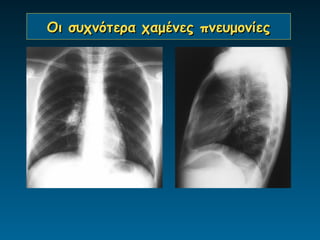

Οι συχνότερα χαμένες πνευμονίες